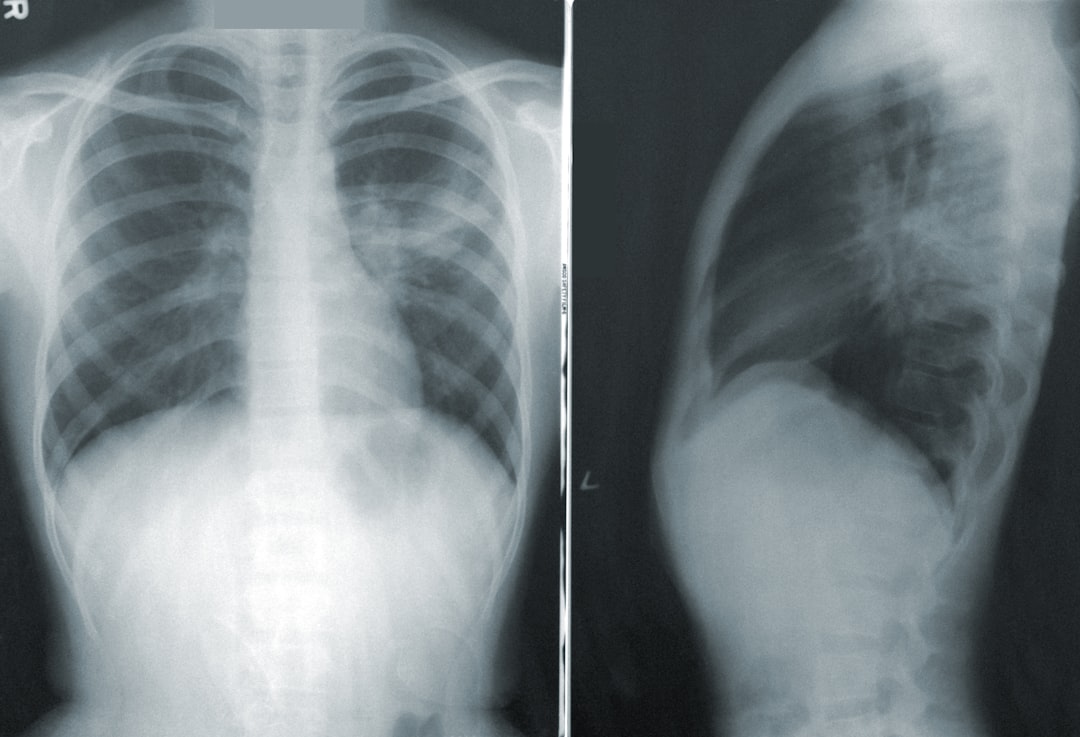

의료기관에 도착하면 우선적으로 필요한 검사를 진행하게 됩니다. 이러한 검사들에는 흉부 X선이나 CT 촬영 등이 포함될 수 있습니다. 이후 검사를 바탕으로 가장 적절한 치료 방법을 의사가 제안할 것입니다. 기흉 치료는 상황에 따라 다르므로, 전문가의 의견을 존중하고 따르는 것이 필요합니다. 기흉 검사의 중요성을 간과하지 않고, 모든 단계를 놓치지 않아서 내 건강을 지키는 것이 좋겠죠!